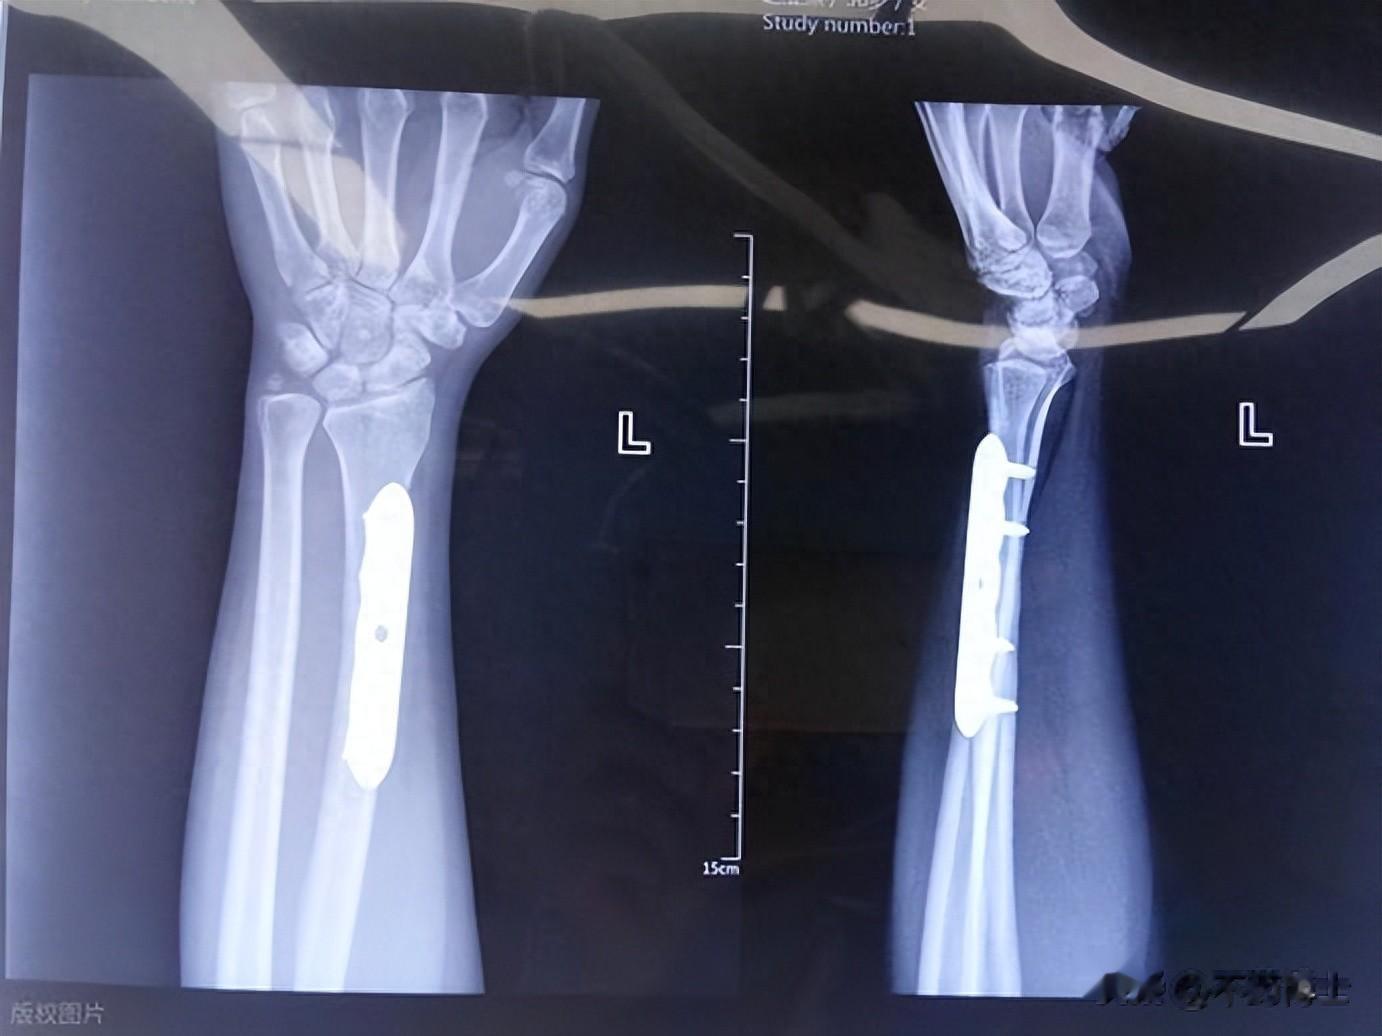

临床研究也证实,四烯甲萘醌软胶囊联合钙剂使用,能显著提升骨密度,还能降低新发骨折的风险(一项纳入241例骨质疏松女性患者的随机对照试验显示,治疗24个月后,联合用药组新发骨折风险明显降低);对于老年骨质疏松性股骨转子间骨折的患者,四烯甲萘醌可以提高术后骨折愈合率达97.5%,促进骨愈合,髋关节功能恢复更好,同时减轻疼痛;对于骨质疏松性骨折的患者,它能有效提高骨密度,减少骨量丢失;它还能有效阻止骨小梁退化,增加骨强度。更值得一提的是,这款胶囊耐受性良好,没有药物假期,适合中老年人长期使用,这对于需要长期干预的骨质疏松人群来说尤为重要。

冬季雪天路滑,骨折风险翻倍,而四烯甲萘醌能有效降低新发骨折的概率。不仅如此,对于做过腰椎椎间融合术、经皮椎体后凸成形术(PKP)、内固定术等骨科手术的患者,它还能促进骨愈合,提高融合率,让术后恢复更顺利。